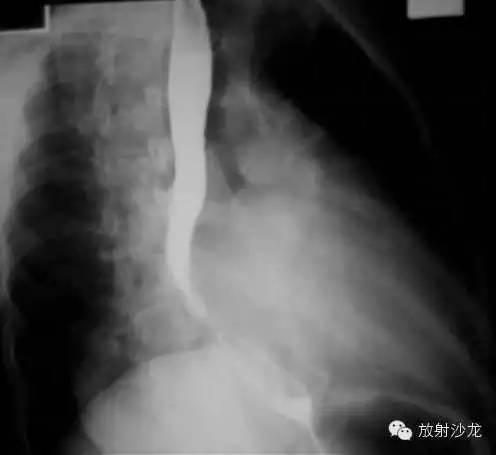

2、左前斜位:心后缘向后下延伸与脊柱重叠,室间沟前下移。

3、侧位:食道前间隙消失,心后间隙变窄。